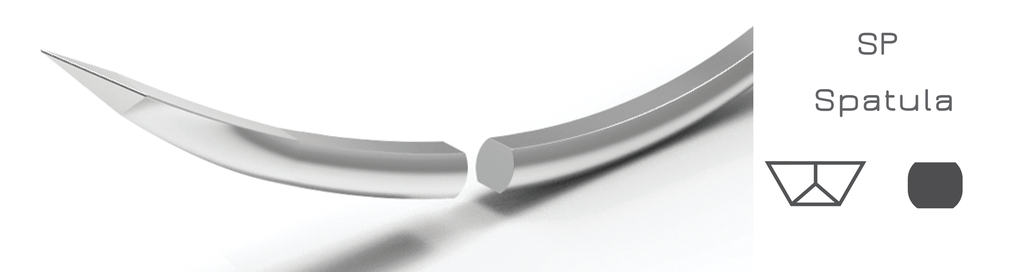

JOST Polyamide USP 10/0 15cm 1 needle spatula 4,0mm 3/8c. Matches with Nylon 10/0 10V33 3mm 15cm 1V1033N1015 (The brand cited in the correspondence is a trademark of the brand owner. All other trademarks are the property of either the Sensuum company or the Akomed - Jost company).